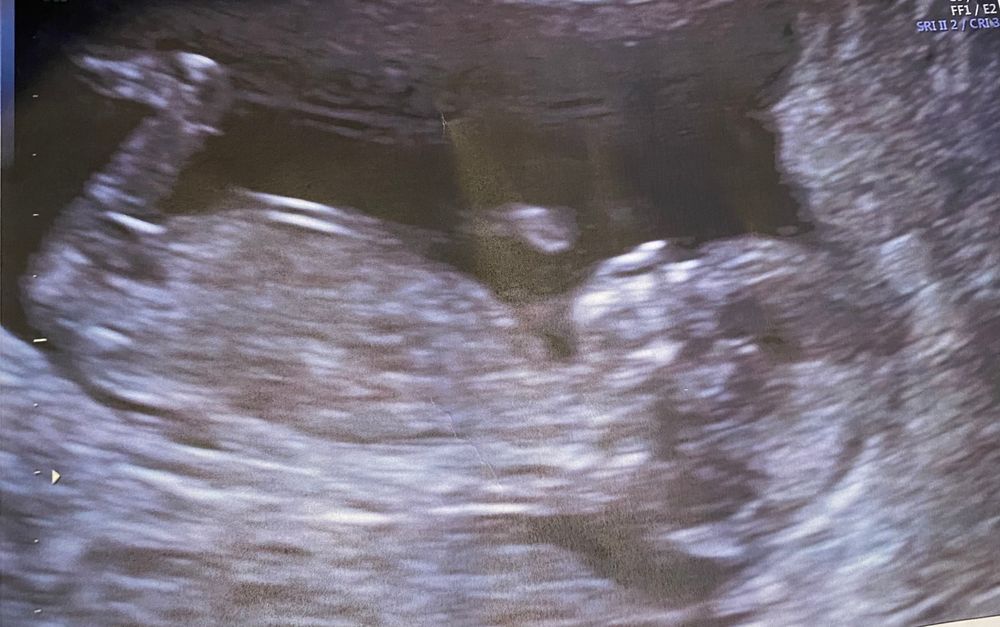

Пол ребёнка в 12?

Если эта палочка - половой бугорок, то да, девочка.

Девочка🌞

Однозначно, я тоже видела что у девочек не просто параллельно, а прямо внизу опущен бугорок

Девочка :)

Я за девочку

Я тоже голосую за девочку)